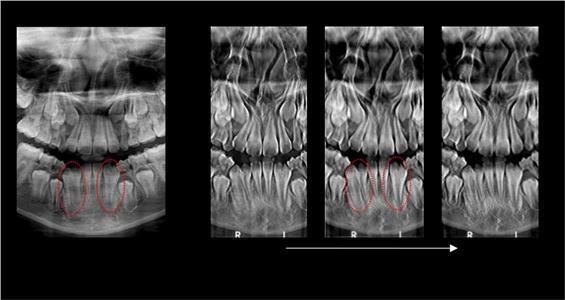

За само 13 секунди се добива високо квалитетна ортопантомграфска снимка, странична смнимка, снимка на вилични зглобови, снимка на синуси. Најновиот Kodak панорамикс има 2Д+ програма со која се добиваат 5 пресека во длабочина за прецизна дијагноза и позиција на импактирани заби и други промени. Со квалитетна панорамска снимка нашиот стручен тим ќе постави точна дијагноза и одреди соодветен план на терапија.